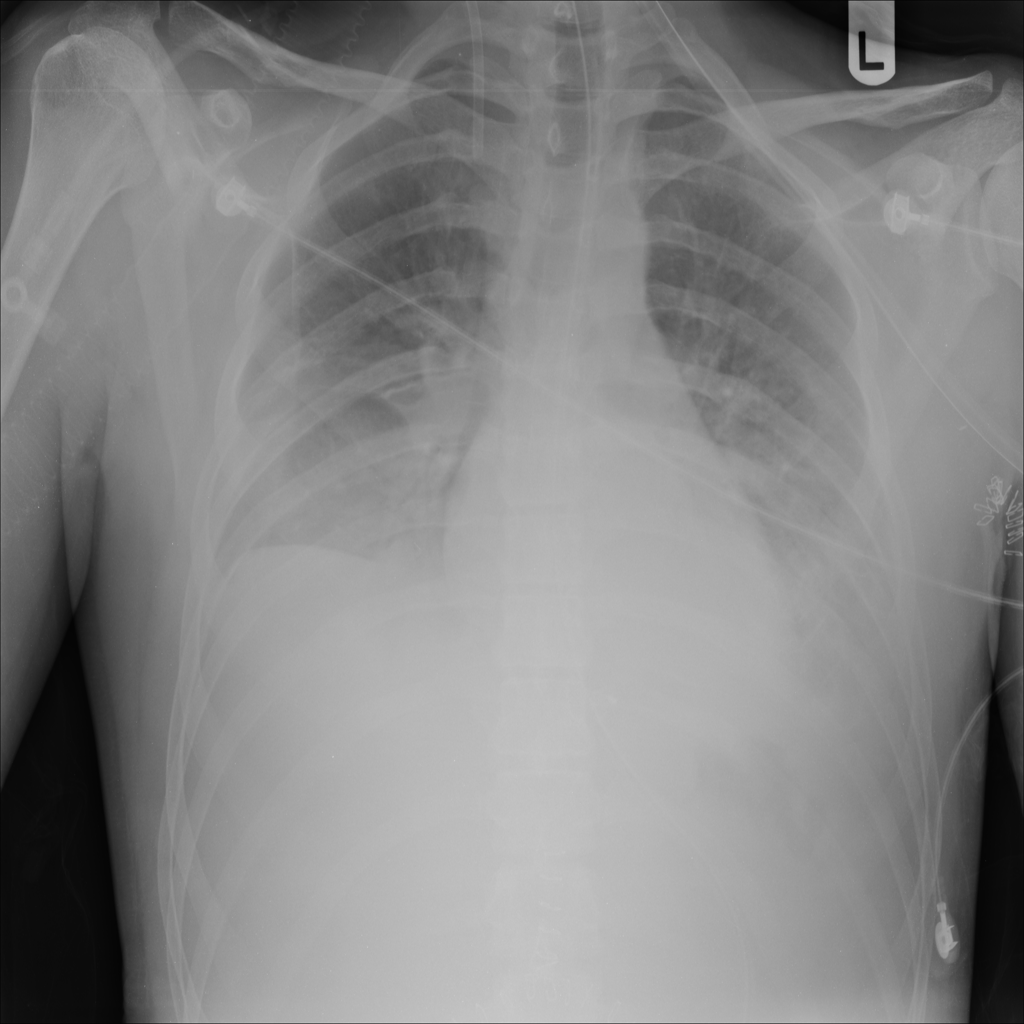

Showing up to 90 reference images for Edema.

PAT-24D9 · IMG-006Edema

PAT-24D9 · IMG-006

AP